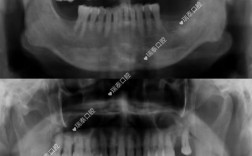

数字化种植牙:即刻负重,当天种牙当天用

针对传统种植牙“手术创伤大、等待周期长”的痛点,星尔门诊引入数字化种植技术:通过CBCT、3D口扫等设备获取口腔数据,利用AI导板设计种植位置,实现“精准到0.1mm”的微创操作,对于骨条件较好的患者,可采用“即刻种植即刻负重”技术,当天植入种植体,安装临时牙冠,当天恢复基本咀嚼功能,门诊开展的单颗/多颗种植、半口/全口种植ALL-ON-4、上颌窦提升等技术,已帮助上千缺牙患者重获好牙。